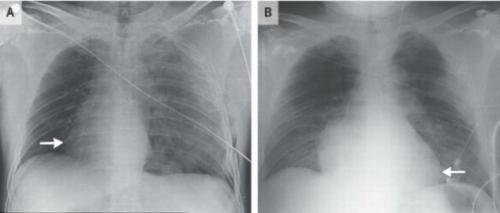

2014-cü ildə italiyalı motosikl sürücüsü qəzaya düşdükdən sonra xəstəxanaya qeyri-adi simptomlarla daxil olub. Onun ürəyi əvvəlkindən fərli olaraq fasilələrlə və zəif döyünməyə başlayıb. Oğlanı müayinə edən həkimlər isə gördüklərinən şoka düşüb. Sən demə qəza nəticəsində oğlanın ürəyi 90 dərəcə sağa fırlanıb. Xoşbəxtlikdən, həkimlər oğlanın ürəyini əvvəlki vəziyyətinə gətirə biliblər.